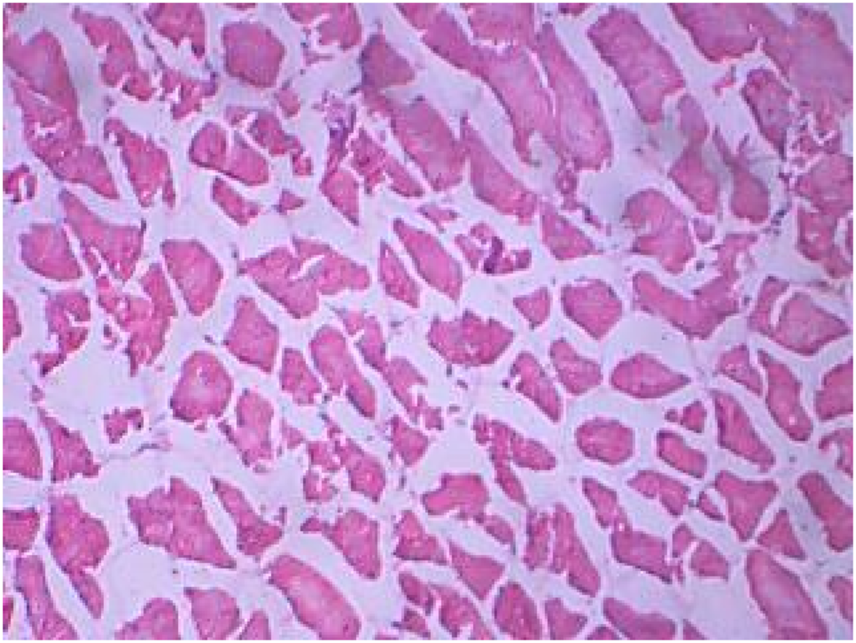

Muscle

The control muscles (Figure 8) showed bundles with striations as usual, while the treated muscles (Figures 8, 9) showed fiber splitting and variation in myofibril diameter. The initial stimulus of DCM can induce hyperactivity and excitability in animals, leading to a release of lactic acid and subsequent muscular fatigue. All these changes were clear as clinical signs at the initial stage of the experiment and were subsequently observed in histopathological changes to muscle (Das and Mukherjee, 2000). Similarly, one of our experiments assessed the cellular stress and histopathology undergone by Oreochromis mossambicus, with biochemical compounds being used as tools or biomarkers to analyze metal contamination. The antioxidative enzymes, cellular biomarkers, AChE, and histopathology can be used as biomarkers for monitoring metal contamination in the aquatic ecosystem. Similarly, one of the studies on Oreochromis mossambicus found that exposure to nanoparticles, such as silver nanoparticles and silicon nanoparticles, induced oxidative stress and cellular alterations, which were reflected in the histopathological studies. Nitschke et al., 1988 reported the inhalation toxicity and oncogenicity of DCM on Sprague-Dawley rats at different concentrations (i.e., 0, 50, 200, and 500 ppm) for 6 h/day and 5 days/week for 2 years. They reported a linear increase in the blood carboxyhemoglobin levels due to the exposure (Kim and Kim, 1996; Kim et al., 2007). Their histopathological studies revealed an increase in hepatocellular vacuolization when exposed to a concentration of 500 ppm. The male and female rats developed multinucleated hepatocytes and a number of spontaneous, benign mammary tumors vigorously progressing to malignant tumors when exposed to 50–200 ppm. There were no significant increases in malignancy at concentrations above 500 ppm. Rooij et al., 2004 reported the toxic effects of both acute and chronic DCM toxicity on fish at 830 μg/L in the marine environment. Thus, this study of DCM toxicity on Oreochromis mossambicus has not been reported anywhere.

FIGURE 8

Control muscle showing muscle fibers.

FIGURE 9

Treated muscle section showing splitting fiber and variation in myofiber diameter.